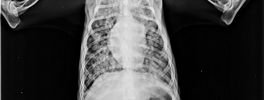

Images

Digital X-Ray